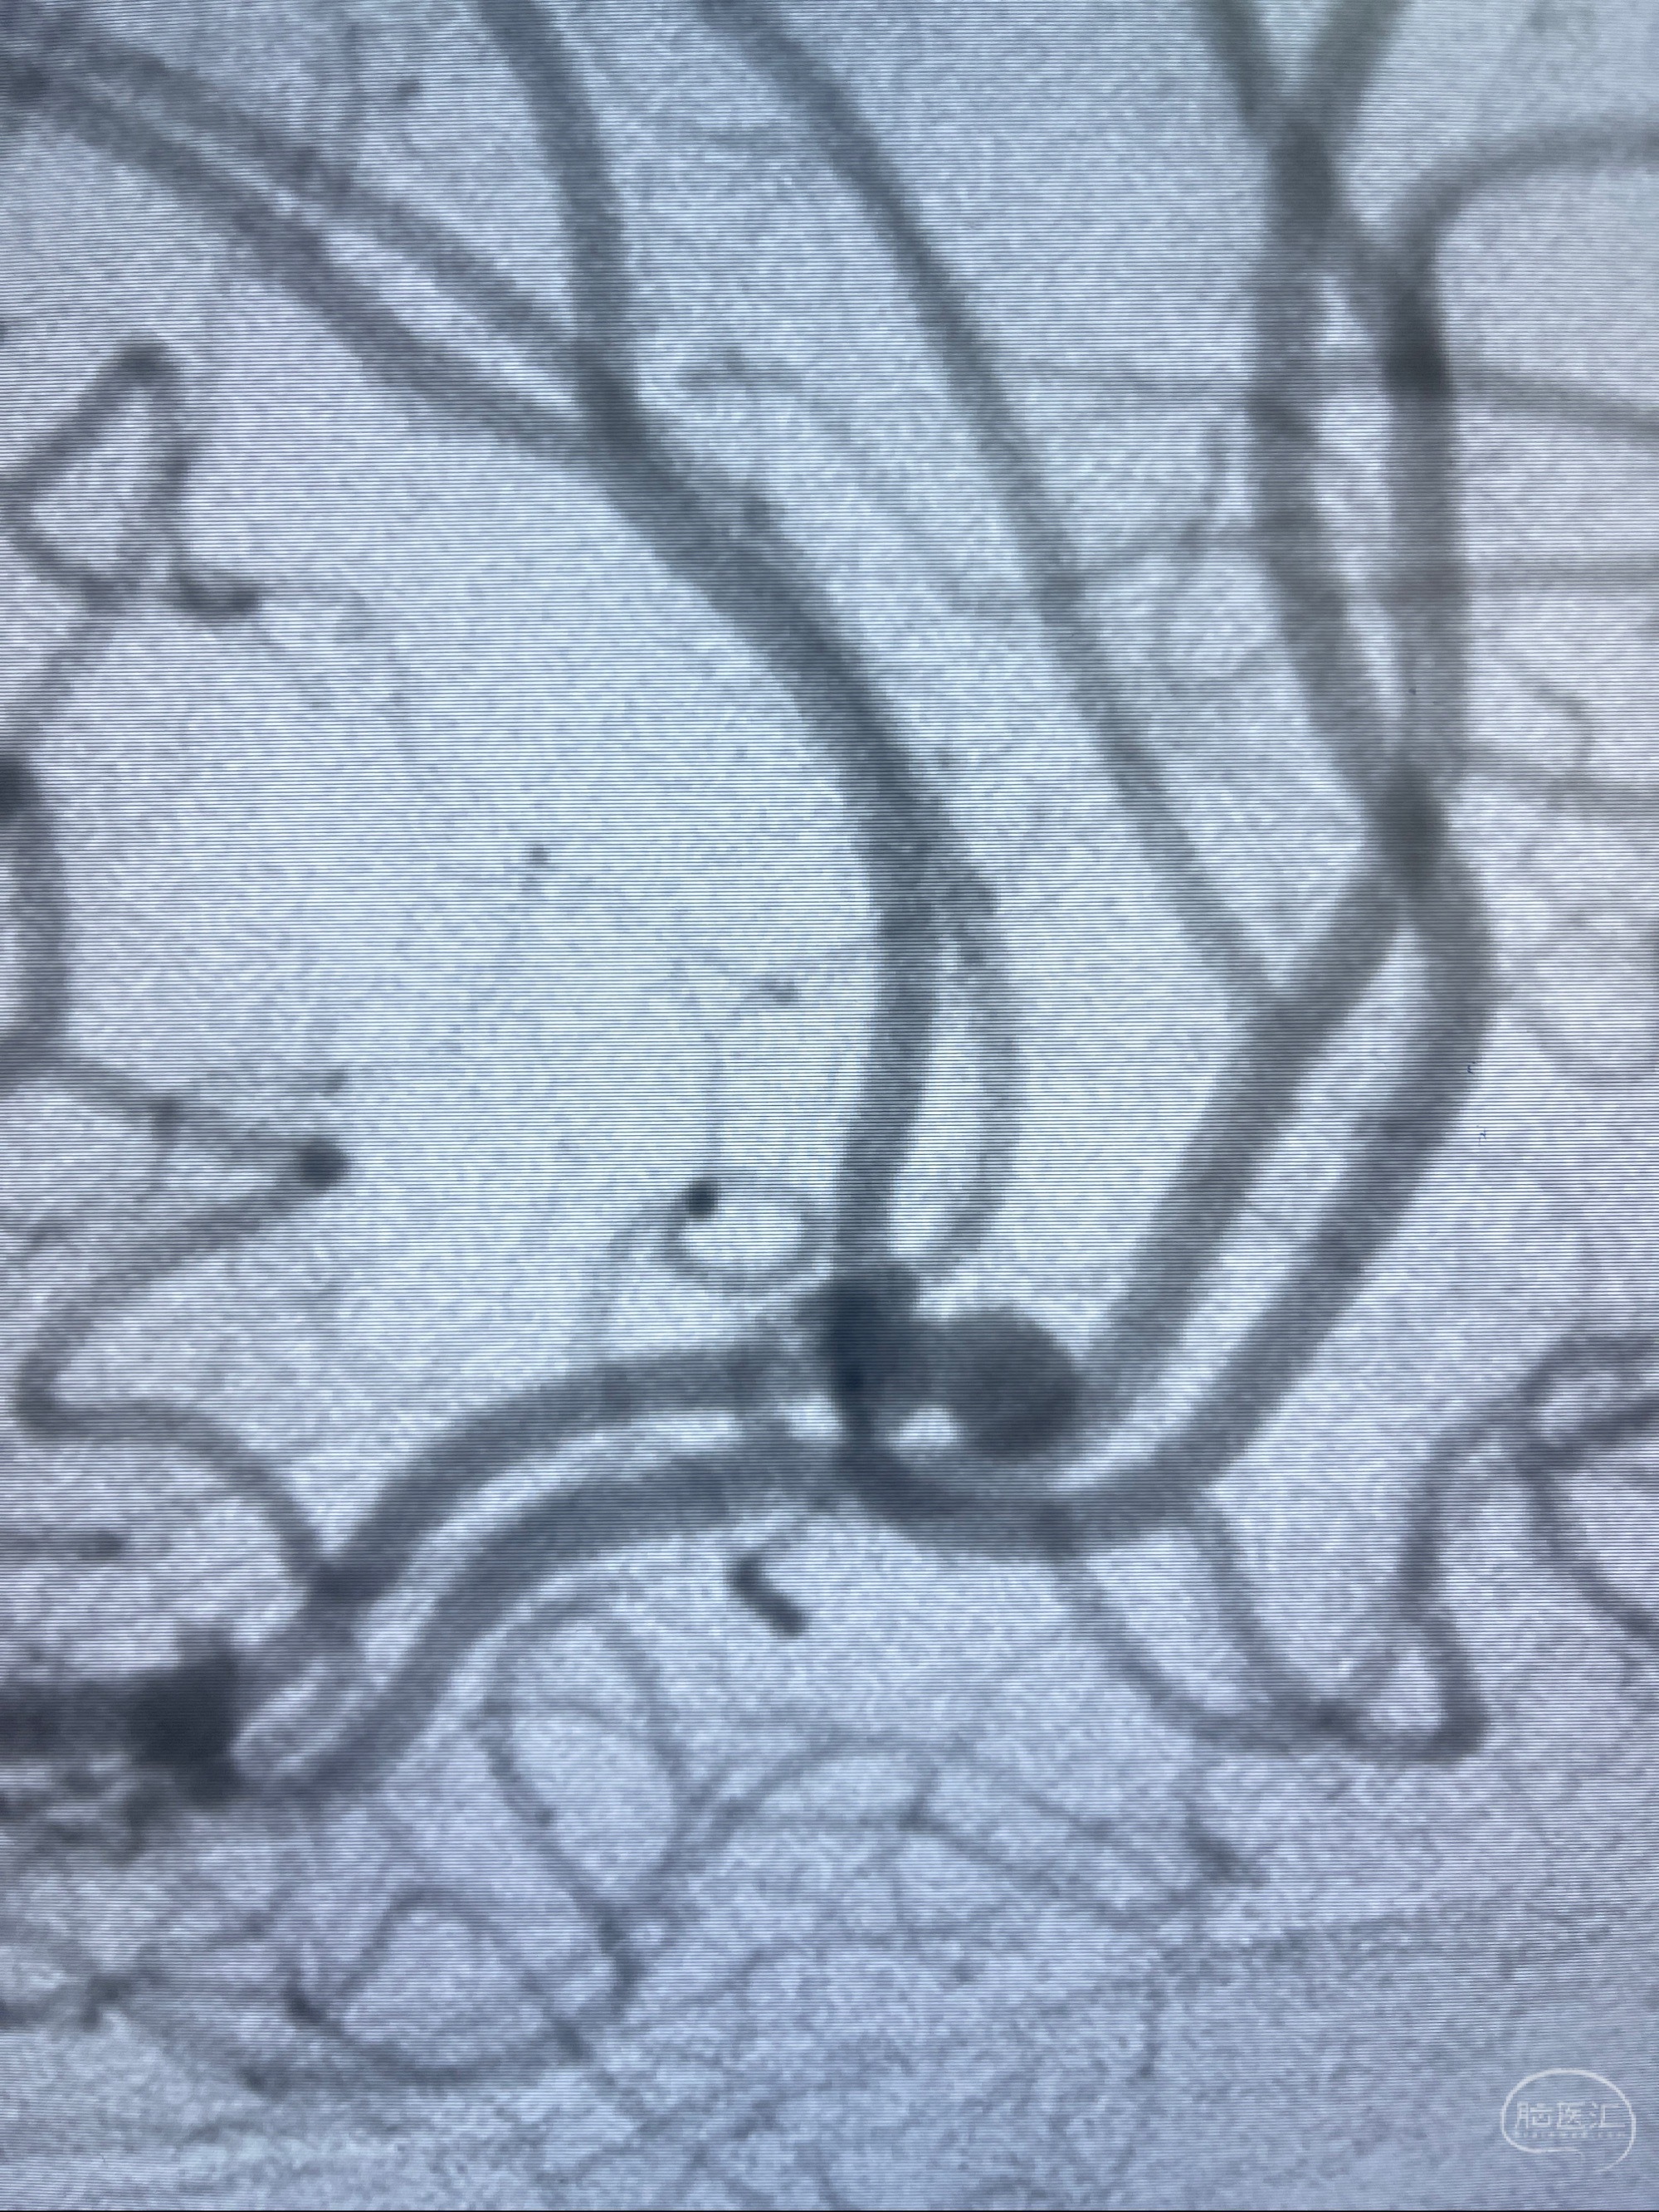

检查;2023-7-18 抚州市第一人民医院 头颈部CTA:左侧大脑前动脉A2段动脉瘤,左侧颈内动脉C4段轻度狭窄,右侧颈内动脉C6段中度狭窄

1.左侧大脑前动脉远侧段(A2-A5)动脉瘤

2023-08-23DSA:左侧前交通动脉瘤,左侧A3/4交界处多发动脉瘤